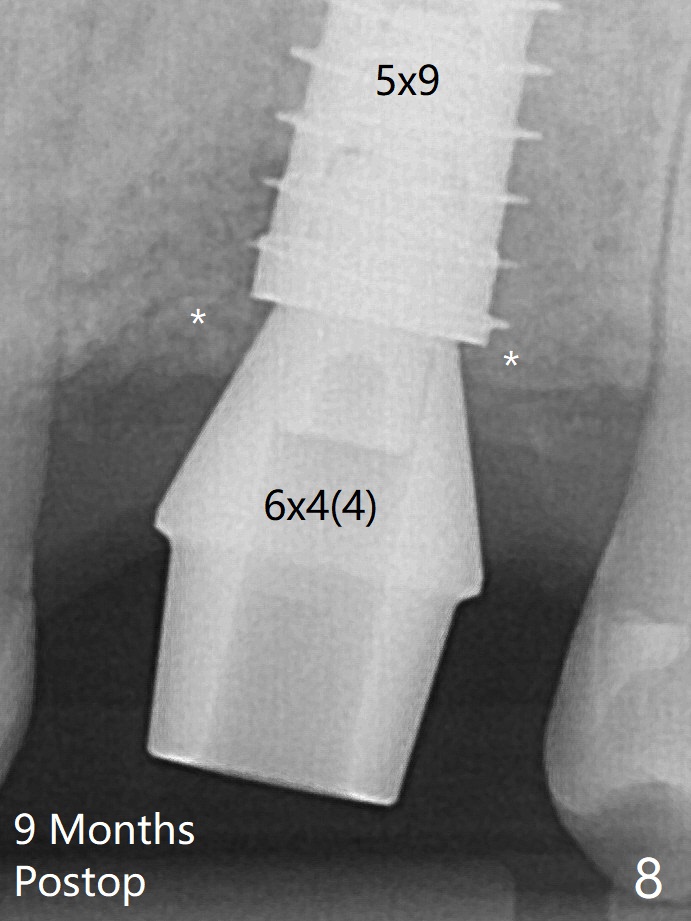

The bone graft is indistinguishable from the original alveolus 9 months postop (Fig.8 *).